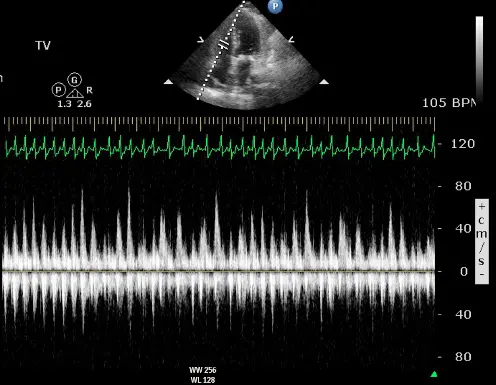

Echo

“Echo diagnosis of constriction is all about pattern recognition” - Sanjiv Shah

Ventricular Interdependence? Think constriction

Constrictive physiology should be considered when evidence of enhanced interdependence is observed by echocardiography.

- Combined parameters from mitral inflow, mitral annular velocities, and hepatic vein velocities have made the diagnosis of constriction and its differentiation from myocardial disease much easier than ever before.3

- Three variables were independently associated with constrictive pericarditis: 1) the presence of ventricular septal shift, 2) medial mitral e’ velocity; and 3) the hepatic vein expiratory diastolic reversal ratio. 2

- Each of these criteria was also significantly associated with constrictive pericarditis in the subset of patients with atrial fibrillation or flutter.

- The presence of ventricular septal shift in combination with either medial e’ ≥ 9 cm/s or hepatic vein expiratory diastolic reversal ratio ≥ 0.79 (Hepatic vein diastolic reversal velocity / diastolic forward flow velocity) was 87% sensitive and 91% specific for the diagnosis of constrictive pericarditis.

- Diastolic septal bounce

- Ventricular interdepence and Respirophasic Variation

- Expiration: mitral inflows ↑, tricuspid inflows ↓

- “When you expire, you increase the pressures in the thorax, but that doesn’t transmit to the LV. And so you have an increased drive from the pulmonary veins to go into and fill the left side. And so in expiration, your mitral inflow goes up. But because of that ventricular interdependence, your tricuspid inflow goes down. And so you have this respirophasic variation in mitral inflow going up with expiration, tricuspid inflow going down with expiration, and then vice versa with inspiration. But for the same exact reason, you get respirophasic shifts in the septum. And so if you do an M-mode through the PLAX view, you’ll see the septum globally shifting towards the right side because the LV is filling during expiration and then shift back towards the left side because the RV is preferentially filling better during inspiration.”

- Mitral inflow ↑ respiratory variation, ↑ E/A, ↓ E deceleration time

- Preserved e’ velocity (septal ≥ lateral)

- By contrast, with restrictive physiology you will expect reduced e’ velocities

- “Your e’ essentially is the tissue velocity of the mitral annulus. And you can look at the medial e’ and the lateral e’. And by definition, restrictive heart disease, there’s a stiffening of the muscle and it doesn’t relax as well. And so the movement of the muscle is low. And so you’ll have a patient with heart failure, preserved ejection fraction, predominant right-sided symptoms, and your e’ will be low, as you suspect, because there’s diastolic dysfunction. However, with constriction, it’s not a muscle disease. And so you may have normal or elevated e’ velocities in the same clinical context or preserved EF. right-sided symptoms with elevated filling pressures. And so normal or elevated e’ tissue Doppler velocities of the mitral annulus can help promote that it’s constriction and not restriction. And alternatively, with the E-prime velocities, you can compare the medial e’ velocity to the lateral e’ velocity. And the normal healthy heart, the septum is a little bit restricted because it’s tethered to the cardiac skeleton. And so normally the lateral e’ has a greater velocity. The lateral mitral annulus moves faster than the medial mitral annulus. But in constriction, because of the tethering of the lateral wall to the constricted, inflamed, fibrous pericardium, you’ll have annulus reversus whereby the medial e’ velocity will be greater than the lateral e’ velocity.”